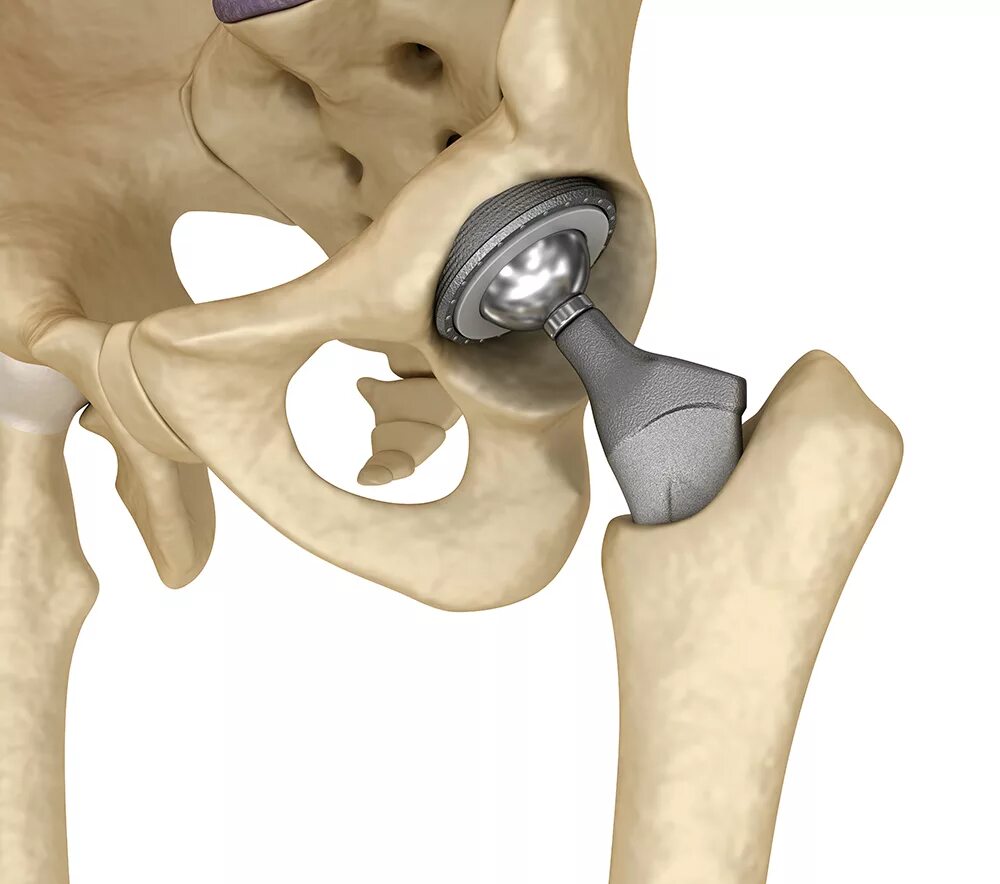

Можно ли эндопротезом делать мрт